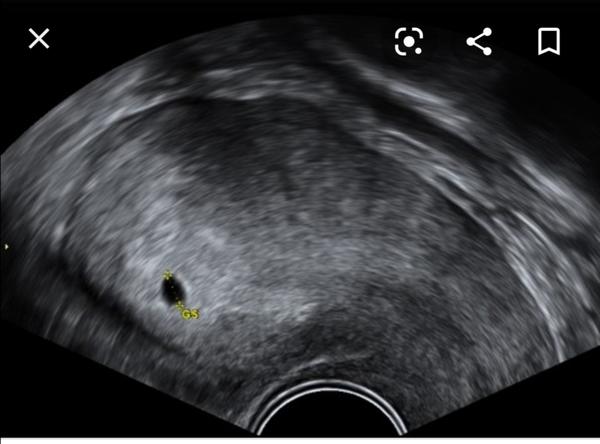

Ahoj, prosím poraďte, dnes jsem byla u dr.posledni ms 1.10.-5.10., 21.10.uvulace. testy pozitivní, ale na utz nic nešlo videt, nejaka pidi mala cerna tecka a pry mam delohu zklonenou dozadu a nějakou tekutinu... ma s tím někdo zkušenost? Mám přijít za týden a docela se bojim ;( testy pekne sílily...

@karolinasvetla111 při zakloněné děloze je možnost, že hned není zárodek vidět, ale pokud lékař tečku viděl.. a mohla být ovulace dýl, na ultrazvuku je zárodek vidět při 1000 jednotkách hcg, vydrž 🙂

@vladienka děkuju za odpověď, doufám, že v pondělí už půjde vidět, ja tam včera měla jen malinkatou černou tecicku ze ani dr nevěděl zda muže potvrdit těhotenství

@karolinasvetla111 já ležela týden v nemocnici kvůli podezření na mimoděložní. Když se ten puntík ukázal, tak jsem potřebovala hmatatelný důkaz, že se mi to nezdálo 🙂

@karolinasvetla111 podle menstruace to měl být 6tt, ale byl to jen 4tt. Později jsem ovulovala 🙂

V 5+3 jsem měla jen 5mm dutinku, v 6+3 už miminko se srdíčkem